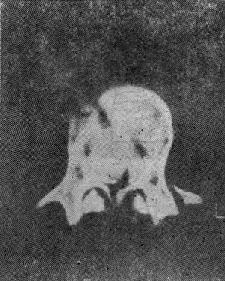

(三)爆裂型骨折 是由沿身体纵轴作用的暴力造成的骨折。椎间盘被压入椎体终板,进入松质骨内致伤。椎体由中央“爆炸”样裂开,将骨折片推向四方,有椎体后缘骨折,且有骨折片突入椎管内(图73-3)。椎弓根之间的距离裂开、增宽。常合并后方椎板的纵行骨折,前方椎体裂开越大,椎板骨折就越明显(图73-4)。有时仅有椎板内板骨折,要CT扫描才能发现。爆裂型骨折又可分成五种:①同时有上、下终板损伤,伴有椎体后缘骨折片突入椎管,压迫脊髓,产生神经系统症状;②椎体上半部骨折,椎体后方压缩,有骨折片旋转进入椎管内,此型最多见;③下方椎体终板损伤;④爆炸型合并有旋转骨折,除有爆裂型骨折特征外,还可见旋转棘突偏歪一侧;⑤爆炸型骨折合并侧方压缩骨折,骨折线斜行过椎体,椎弓根距离增宽,椎体两侧高度不一样,常伴有多发横突骨折,此型最不稳定。

图73-3 爆裂型骨折

图73-4 椎板纵行骨折

爆炸型骨折的主要特点为:椎弓根间距增宽,椎体后部压缩,高度变小,及椎体横径增宽。几乎所有爆裂型骨折都具有神经系统症状。